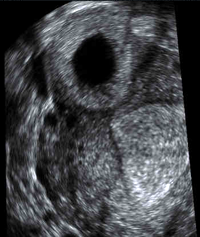

Gynecologic Imaging

UCSF‘s ultrasound subspecialty uses state-of-the-art, multimodality approach to gynecologic imaging processes (including endometrial evaluation with and without saline infusion) to diagnose ovarian and uterine pathology as well as complications of early pregnancy, including ectopic pregnancy. We contribute to improved patient outcomes by using image guidance for methotrexate injections and bedside sonography in the operating room in challenging gynecologic surgeries.

C-section scar ectopic pregnancy.